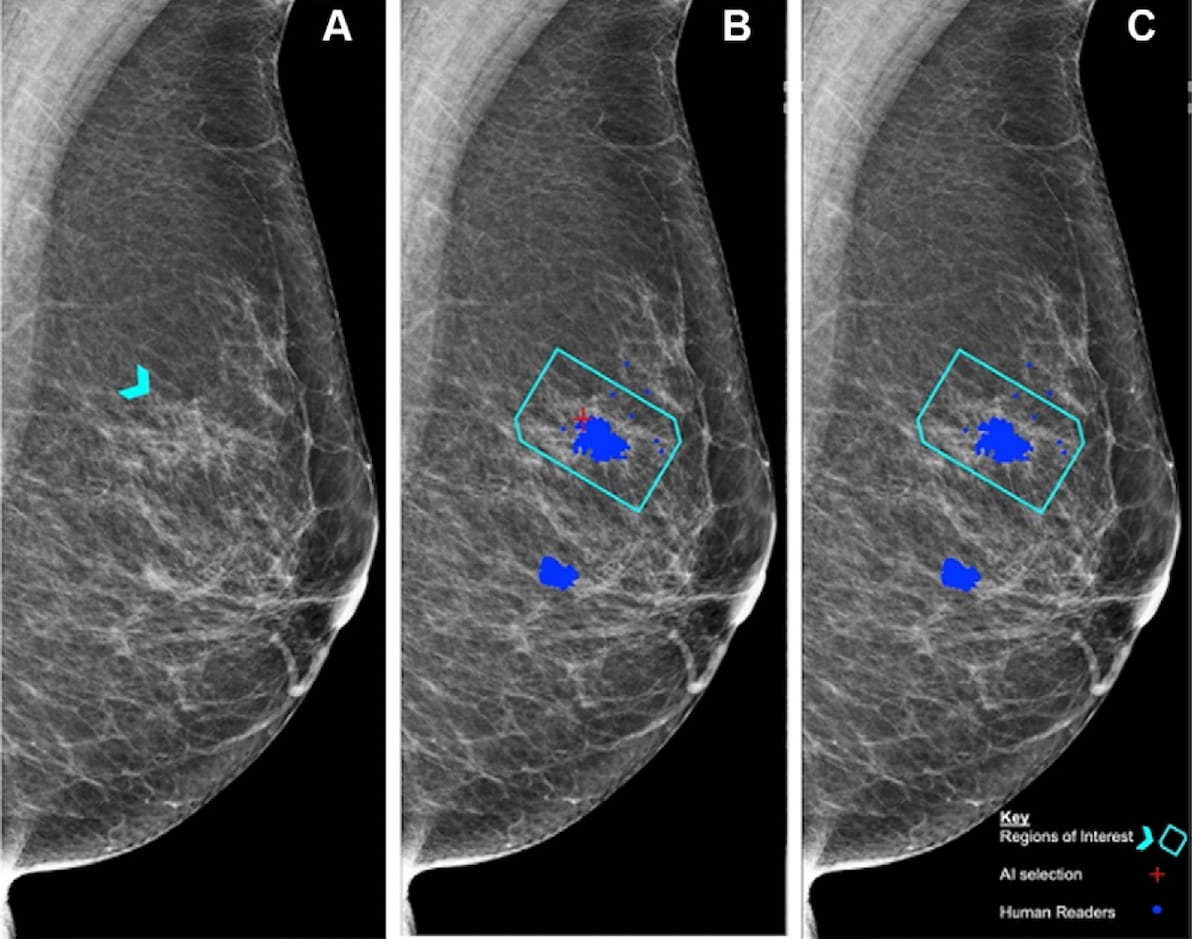

Reportedly the first randomized trial to examine the impact of artificial intelligence (AI) on screening mammography, researchers found AI-aided screening led to a 20 percent increase in breast cancer detection and a 44.3 percent decrease in mammography screening workload.